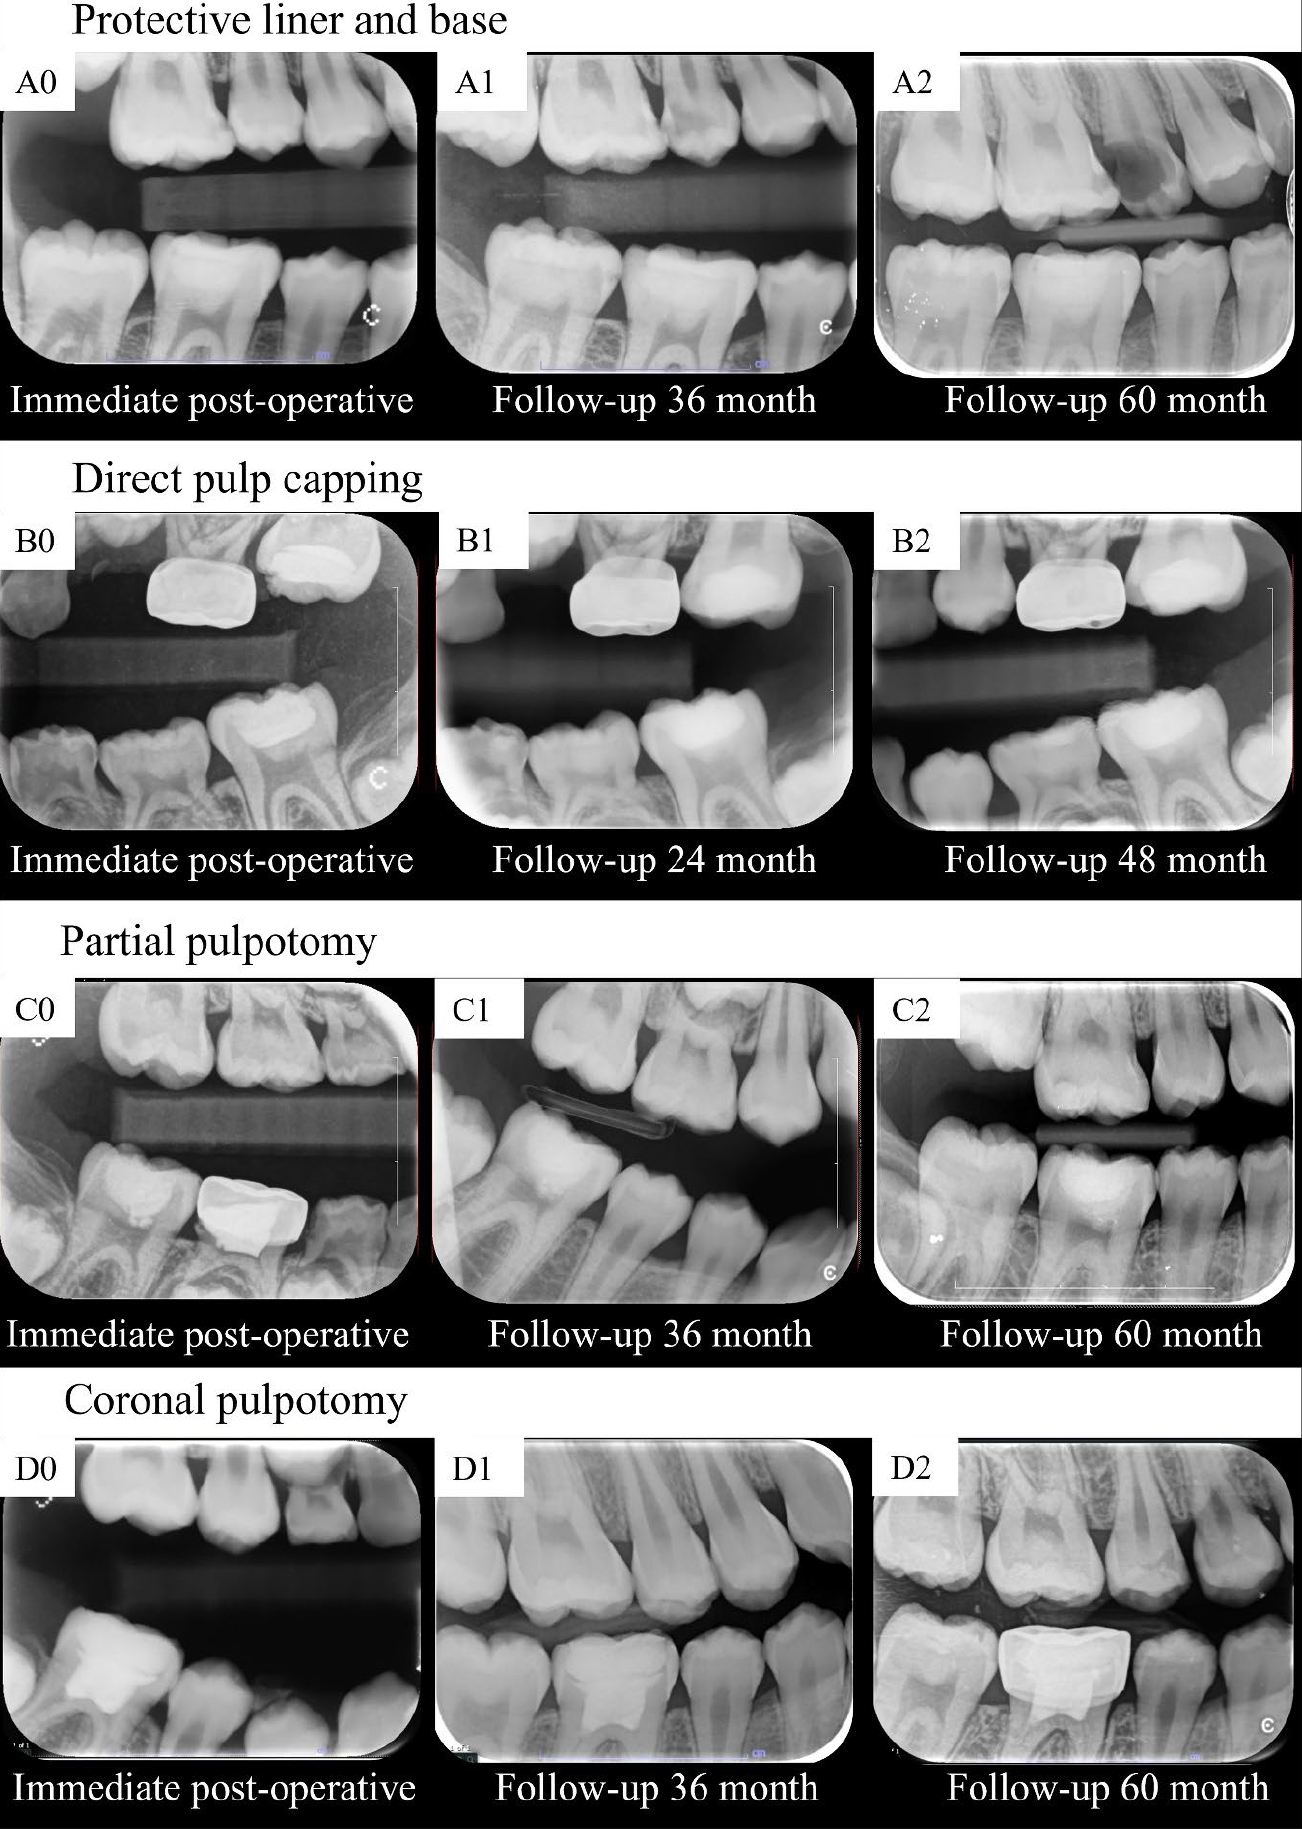

Type of vital pulp therapy

Figure 3 illustrates changes from baseline in pulp/tooth proportion values in the DPC, PP, and CP groups against those in the LB group. Notably, for the ∆A1/A0 value, changes were significantly greater in the PP group than in the LB group at 12, 18, 24, 30, 36, 48, 60, and 72 months in Figure 3A. In contrast, the changes in ∆B1/B0 of the CP, PP, and DPC groups did not significantly differ from those of the LB group at any follow-up point in Figure 3B. Furthermore, for ∆B2/B0, decreases were significantly greater in the CP group than in the LB group at all follow-up points, except at 6 months (Figure 3C). Finally, for ∆C1/C0, decreases were significantly greater in the PP group than in the LB group at 60 and 72 months in Figure 3D. Figure 4 illustrates different magnitudes of pulp space narrowing over time in different types of VPT cases. The fixed- and random-effects models for changes from baseline in pulp/tooth proportion values (ΔA1/A0) in the DPC, PP, and CP groups compared with those in the LB group, including their marginal predictions and pairwise contrast p-values, are presented in Supplementary Tables 13–24.

Comparison of the changes from baseline in pulp/tooth proportion values (A–D) in the DPC, PP, and CP groups against those in the LB group. LB, protective liner and base; DPC, direct pulp capping; PP, partial pulpotomy; CP, coronal pulpotomy. *p < 0.05, statistically significant.